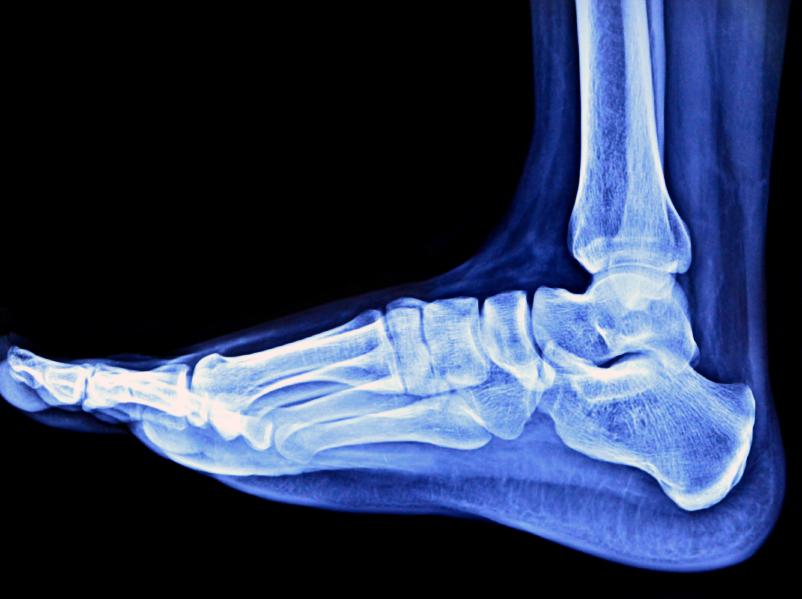

El pie plano es una condición podológica común que se presenta cuando los tendones de nuestros pies no son lo suficientemente firmes y tensos como para formar el arco plantar, dando como resultado un pie de apariencia plana que puede traer consigo diversas molestias y condiciones articulares que resulta importante corregir. Aunque en la mayoría de los casos la falta de arco no genera dolor, esta condición puede interferir de forma importante con la marcha afectando nuestra capacidad para realizar determinados deportes e incluso para andar largas distancias. En unComo.com te explicamos con detalle cómo tratar los pies planos.

El primer paso para tratar los pies planos es visitar a un podólogo pues solo un especialista en esta materia podrá determinar que, efectivamente, contamos con este problema. En la mayoría de los casos el pie plano no genera ningún dolor, sin embargo puede ocasionar a mediano y largo plazo lesiones en articulaciones como los tobillos o las rodillas, al tiempo que genera fatiga en los pacientes que se cansan al caminar distancias largas o moderadas.